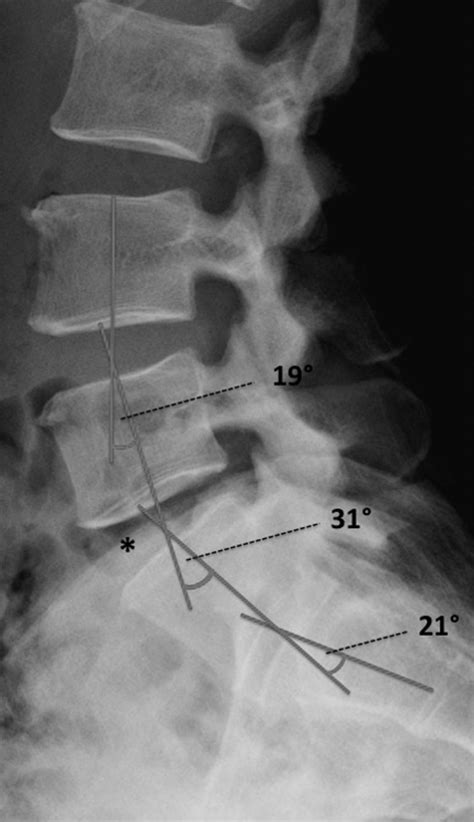

Accurate diagnosis of conditions affecting the lumbosacral transitional segment is essential for effective treatment. Several diagnostic methods are commonly used to evaluate this region:

• Imaging Studies: Imaging techniques such as X-rays, MRI, and CT scans are crucial for visualizing the anatomy of the lumbosacral region. These studies can reveal degenerative changes, herniated discs, spinal stenosis, and other abnormalities.

Spondylolysis is a condition characterized by a defect or fracture in the pars interarticularis, a small bone in the vertebrae. This condition is common in athletes who engage in repetitive hyperextension of the spine, such as gymnasts and football linemen. Spondylolisthesis, the forward slippage of one vertebra over another, can occur as a result of spondylolysis or other degenerative changes in the spine.